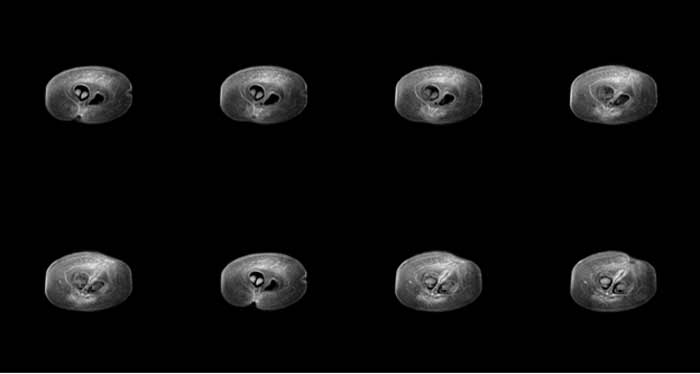

成像实验数据 —小鼠腹部成像图